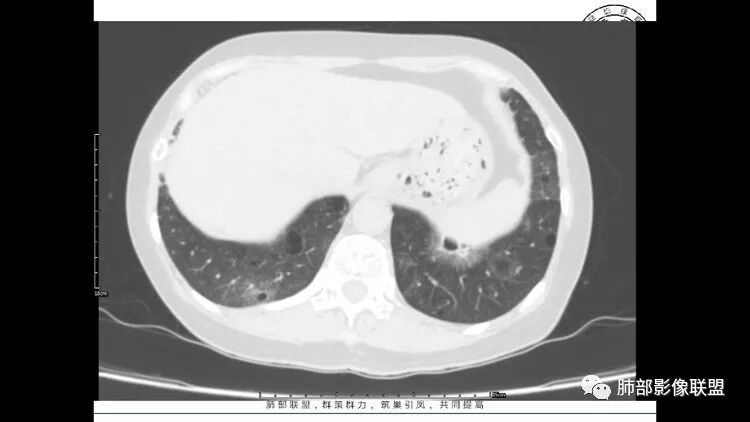

胸CT:1.双肺多发囊性变,以中下肺为主,病变边缘可见肺动脉,部分囊内可见分隔及肺动脉,双下部分肺野周围可见小叶中心结节及树丫征。

2 左肺上叶尖后段 右肺上叶前段 右肺下叶外基底段 结节影,边界清楚,可见柔软毛刺,左肺下叶后基底段混合密度影。

患者中年女性,因右眼红痛1天就诊。胸CT:双肺多发囊性变及结节影,囊以中下肺为多,部分囊内可见分隔及肺动脉,结节部分为实性,部分为混合性,边缘光滑,未见明显毛刺、棘突、胸膜牵拉及血管集束征象。双中下可见支气管扩张及树丫征。淋巴结无明显肿大。综合考虑:一元淋巴细胞间质性肺炎。多元鉴别肺腺癌并转移等恶性病变。

中年女性,因“角膜炎”入院,自用眼液2年,(眼干?)肺部:双肺多发类圆形薄壁气囊+实性结节+GGO,下肺分布为主,纵隔淋巴结肿大,考虑淋巴系统增殖,LIP可能性大,可能继发于干燥综合症;左肺下叶的混合磨玻璃结节形迹可疑,边界清晰,内部疑似空泡,扩张扭曲支气管,极像肺癌,伴双肺转移?待排吧

左肺下叶混杂密度病灶,其内可见空泡,周围ggo清楚,考虑浸润性腺癌。双肺散在多发薄壁囊腔和实性结节,以胸膜下及血管旁分布位于,气囊可见血管贴边征,双肺小叶间隔及中央间质增厚,局部可见磨玻璃影及树芽征,纵隔内淋巴结肿大,考虑LIP

综上,考虑左下肺浸润性腺癌+LIP

双肺多发大小不等囊腔,可见薄壁,部分囊腔内可见血管影,伴双肺多发结节,结合患者眼病及类风湿病史,考虑LIP可能大。另左肺下叶磨玻璃结节,边界清晰,内可见空泡,伴纵膈多发肿大淋巴结,不除外浸润性腺癌可能。

老年女性,长期使用激素史。双肺多发散在斑片状磨玻璃密度影及大小不等的薄壁含气囊腔,下肺相对较多较大。双肺多发结节,左肺上叶结节相对较大,界清,边缘光滑,分叶不明显。右肺下叶前外底段散在树丫。前上纵膈偏左侧不规则软组织团块,颗粒感,偏软。肺内囊腔及磨玻璃影考虑淋巴细胞间质性肺炎,或淋巴管肌瘤病。纵膈团块考虑淋巴管瘤。两者结合,考虑淋巴细胞增生病变。右肺下叶散在树丫,结核待排。双肺结节性质待定。

双肺多发散在斑片状磨玻璃密度影及大小不等的薄壁含气囊腔,下肺相对较多较大。双肺多发结节,界清,边缘光滑,分叶不明显。右肺下叶前外基底段散在斑片树芽。前上纵膈偏左侧不规则软组织团块,密度不均,其内可见不规则纤维样低密度,周围簇状小淋巴结。考虑1淋巴细胞间质性肺炎。2考虑纵膈胸腺淋巴瘤。

LIP影像重要线索一句话:

双肺下叶分布为主的间质改变(磨玻璃影、小叶间隔增厚)、散在气囊影(常有血管贴边)、边界不清小结节